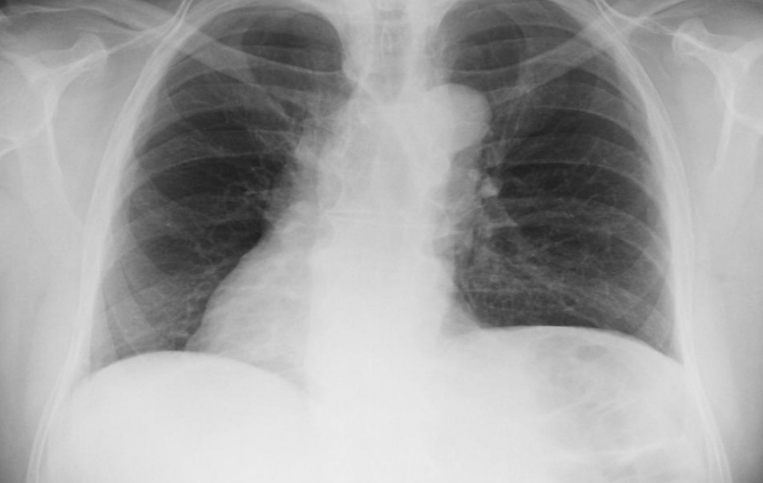

COPD patient

diaphragm flat

barrel chest on lateral view (AP diameter increase)

widened intercostal spaces

lungs hypper enflated→globular heart